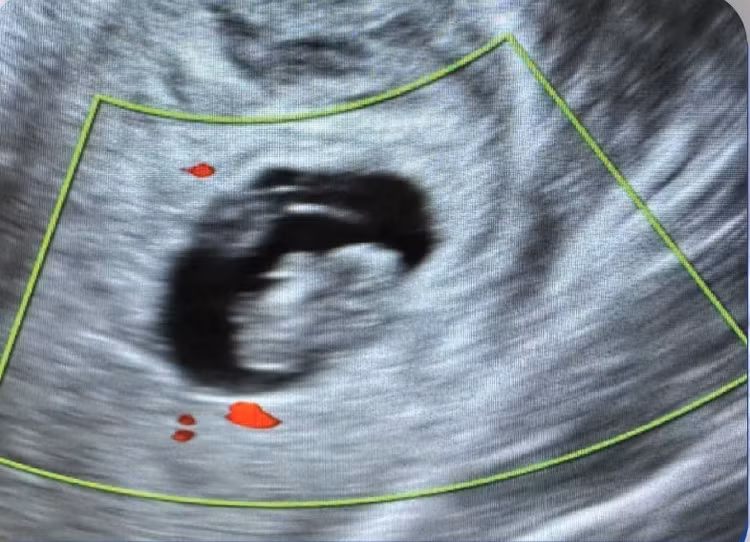

Kết quả siêu âm vỡ khối chửa ngoài tử cung - Ảnh BVCC

Qua thăm khám ban đầu, các bác sĩ Khoa Phụ sản – Bệnh viện Hữu nghị Lạc Việt ghi nhận bệnh nhân có dấu hiệu thiếu máu nặng, da xanh, niêm mạc nhợt, choáng, bụng chướng và có phản ứng thành bụng. Ngay lập tức, bệnh nhân được chỉ định siêu âm khẩn cấp.

Kết quả cho thấy túi thai ngoài tử cung bên phải, tương đương khoảng 8 tuần tuổi, không có tim thai và ổ bụng có nhiều dịch máu.